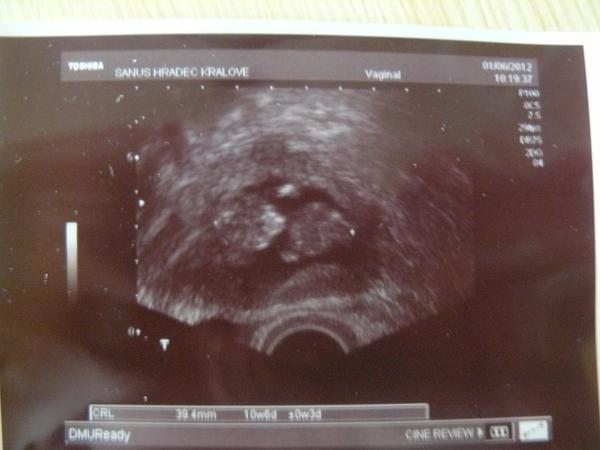

Ahojte holky, tak jsem byla dnes v HK v Sanusu, byl semnou můj miláček. Z prvu se začal zdráhat, že nepůjde dovnitř, ale pak šel jinej tatínek a tak se taky osmnělil. Dnes byl UTZ jen na zjištění velikosti miminka, aby nás objednali už přesně na NT screeneng na 14.6., ale i tak nám pan doktor ukázal monitor oběma a miminko na nás mávalo obouma ručičkama a kopalo nožičkama 😀 Ukázal jak mu tluče srdíčko, no byla to nádhera, i manžel pak když jsem šla ještě zaplatit a na krev, se rozplíval nad fotečkou v čekárně 😀 Jinak miminko to nakonec dohnalo asi, a nebo je samozřejmě kvalitnější UTZ a vycházíme na TP 22.12., tedy dnes 10+6 a od minulé středy jsme povyrostli o 1,4cm. Tak ještě aby to hlavně příště bylo všechno OK 🙂